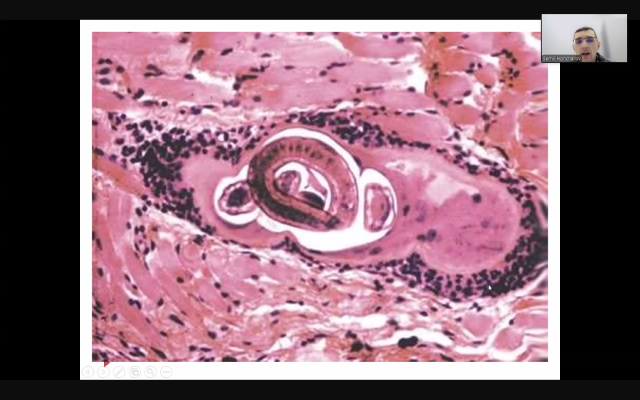

• Паразитарні загрози: глобальний погляд. Окреслено актуальність та шляхи боротьби з транскордонними паразитозами, такими як трихінельоз і цистицеркоз, що становлять небезпеку як для тварин, так і для людей, особливо в умовах міжнародної торгівлі.